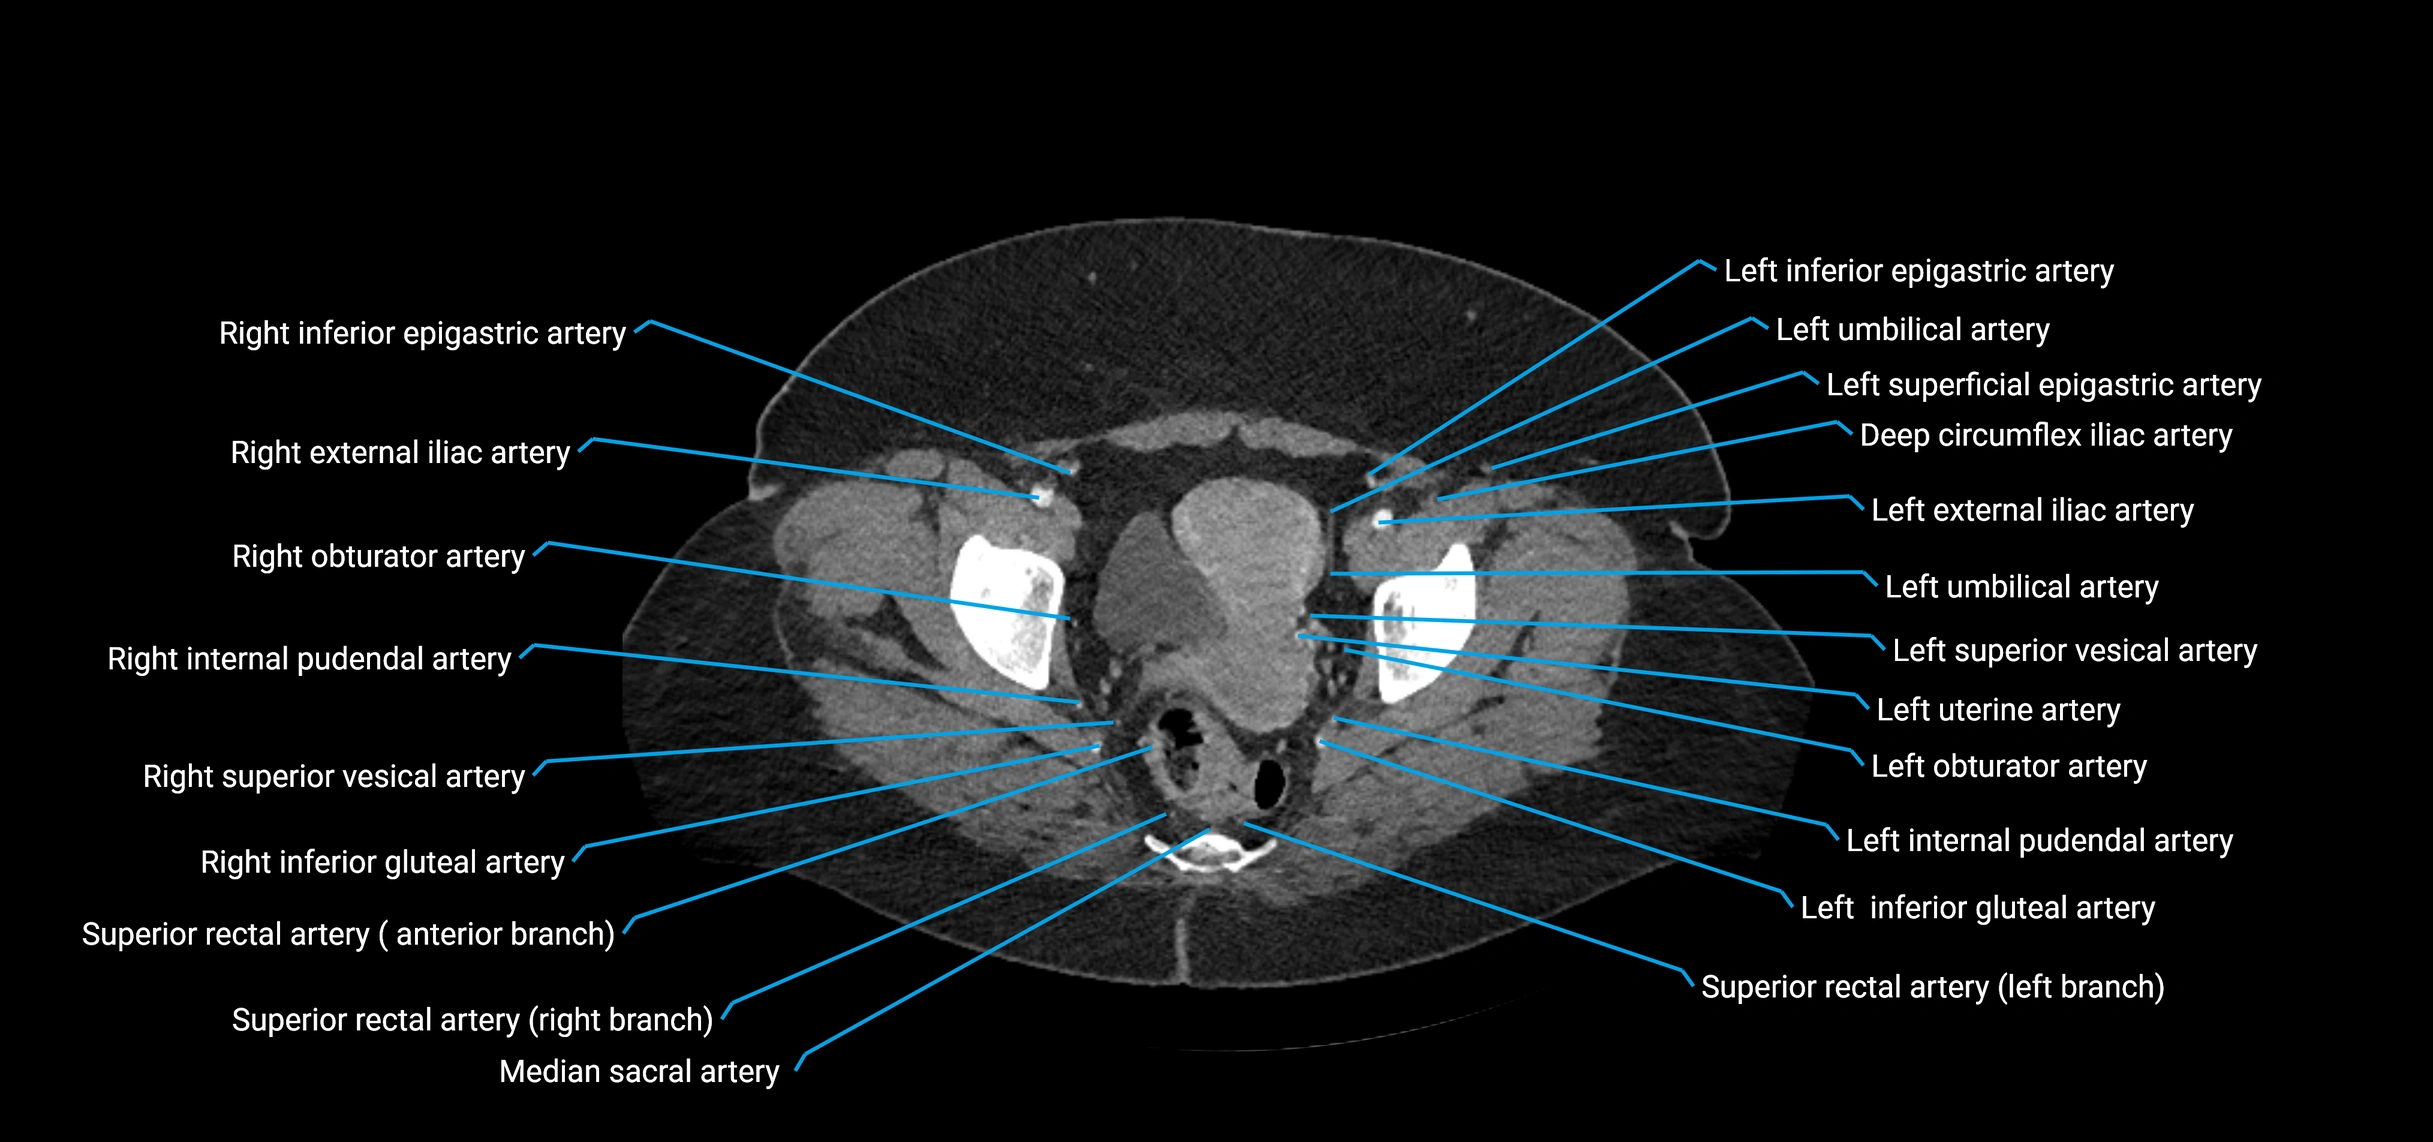

CT Appearance

Non-contrast CT:

• Appears as a tubular soft tissue structure anterior to vertebral bodies

• Calcified atherosclerotic plaques appear as hyperdense foci along the wall

• Useful for screening abdominal aortic aneurysm (AAA) size and mural calcification

Contrast-enhanced CT (CTA):

• Gold standard for abdominal aortic imaging

• Provides excellent detail of lumen, wall, aneurysm, thrombus, and branch vessels

• Multiplanar and 3D reconstructions help in aneurysm measurement, stent graft planning, and dissection evaluation

• Detects acute rupture, traumatic injury, or occlusion with high sensitivity

CT images

image